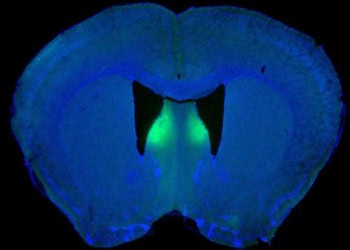

Read moreDetailsViolent, unprovoked outbursts in male mice have been linked to changes in a brain structure tied to the control of...

Read moreDetailsResearchers at NYU Langone Medical Center say they have added to evidence that a shell-shaped region in the center of...